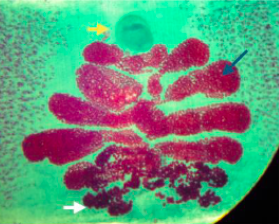

What is this?

A

Larval stage of T.Solium

How well did you know this?